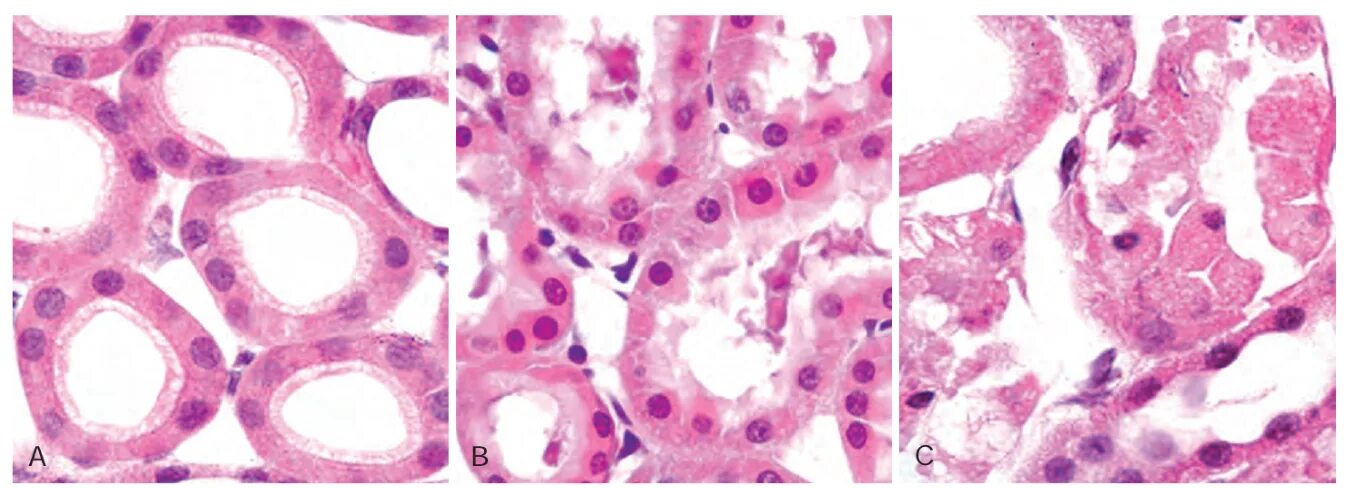

Reversed cell